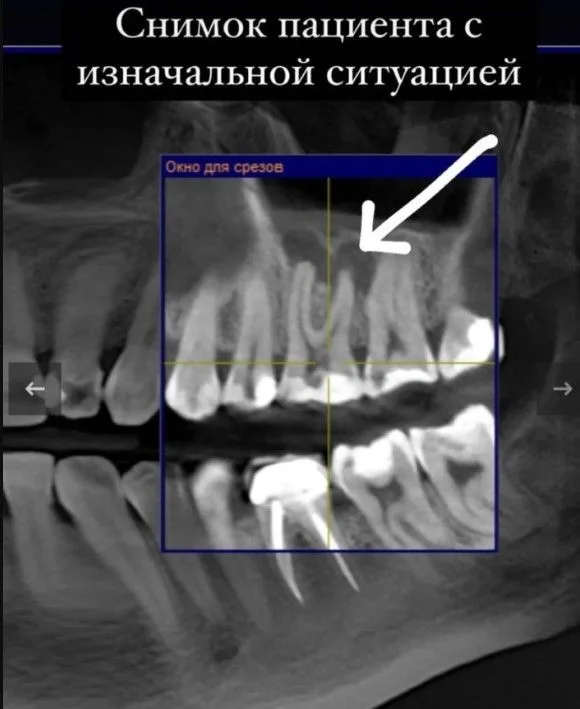

Случай из практики - ко мне обратилась пациентка. В другой клинике случайно(!) на 3D-снимке нашли воспаление в ранее леченном канале зуба. Оттуда направили к нам. К моменту визита в нашу клинику, у пациентки уже был хронический апикальный периодонтит из-за пропущенного второго мезио-буккального канала.

хронический апикальный периодонтит

Залог успеха обработки МБ2 – понимание того, где надо его искать и умение работать с дентальным микроскопом. Было проведено КТ на высокоточном томографе. Диаметр канала зуба меньше миллиметра, но под микроскопом канал был пролечен максимально точно. Лечение проведено с постановкой кальция на 2 недели и последующей обтурацией. Контрольный снимок сделали у нас спустя 1,5 года - воспаления нет.